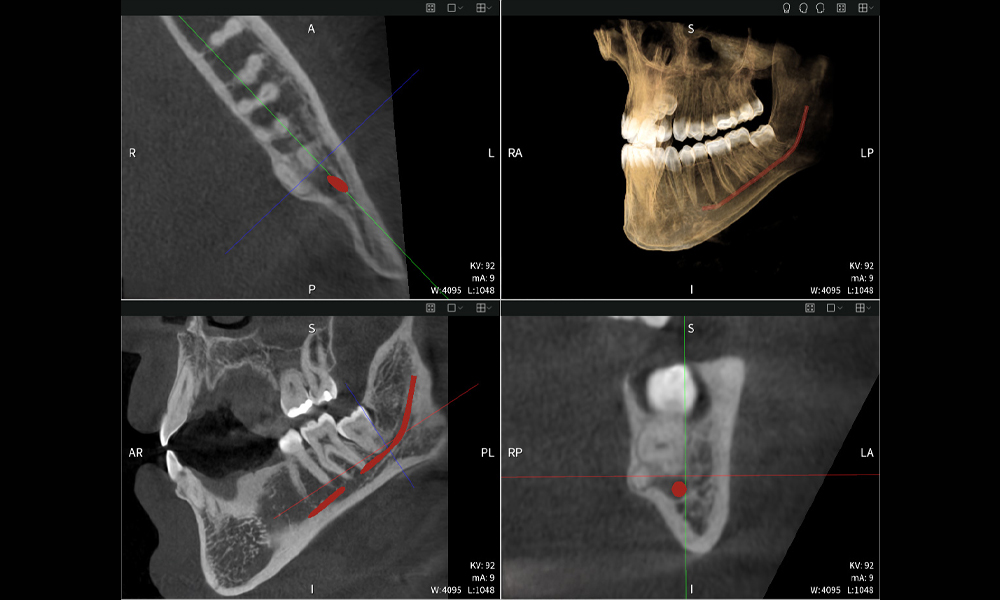

Figura a: Resultados de imagen de Seethrough Max, sobre un fondo negro.

Figura a

• Arriba a la izquierda: Corte axial de la mandíbula izquierda (región 38) que muestra el nervio alveolar inferior (en rojo) en proximidad a las raíces del diente 38.

• Arriba a la derecha: Reconstrucción 3D de toda la mandíbula para orientación. El nervio alveolar inferior marcado en rojo ilustra su ubicación dentro del hueso mandibular.

• Abajo a la izquierda: Vista sagital de la mandíbula (región 38), destacando la estrecha relación espacial entre las raíces y el conducto del nervio.

• Abajo a la derecha: Vista coronal de la mandíbula (región 38), crucial para evaluar la posición espacial de las raíces en relación con el nervio.